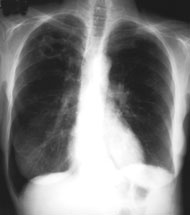

Eine 70-jährige Patientin meldet sich bei Ihnen in der Praxis mit Verschlechterung des Allgemeinzustandes seit 4-5 Wochen und Fieber bis maximal 38.5 Grad.

Des weitern klagt sie über einen trockenen Husten. Ausser einer arteriellen Hypertonie besteht als Vorerkrankung eine leichte COPD. Da Sie ausser dem Husten keinen klinischen Fokus für einen Infekt finden, entschliessen Sie sich für ein Thorax-Bild. Optimalerweise haben Sie sogar noch ein pa-Thorax von vor 2 Jahren zum Vergleich:

Thorax pa aktuell

Bild vergrössern